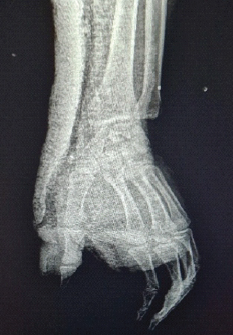

Complex Volar Carpometacarpal Dislocation with Concomitant Thumb Interphalangeal Injury: A Case Report

Layes Touré , Moussa Sidibé , Térédjou Fatou Sanogo , Aliou Bah , Abdoul Kadri Moussa